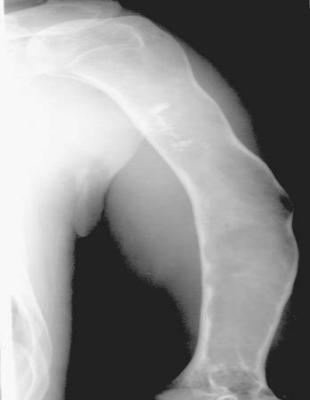

3.强直性脊柱炎 ( AS):以中轴关节慢性炎症为主的全身疾病,病因不明,类风湿因子阴性。病理学:非特异性炎症。;双侧骶髂关节受累;

脊柱韧带骨化—骨性强直—竹节状脊柱

病理改变:渗出轻,增殖为主。;韧带和关节囊的附着部炎症,导致韧带骨赘形成、椎体方形变、椎骨终板破坏、跟腱炎等。;易软骨化生及骨化。

X线表现:1.骶髂关节鼠咬状骨质破坏,狭窄或骨性强直,双侧对称;2.竹节状脊柱,纤维环和韧带的骨化、椎体方形变